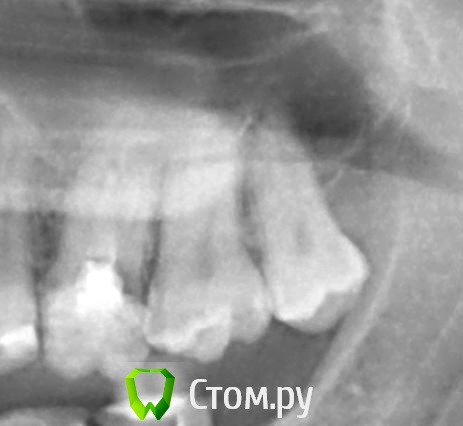

Zenden Опубликовано 19 декабря, 2013 Поделиться Опубликовано 19 декабря, 2013 (изменено) Всем добрый день, вот такой вопрос: Месяц назад лечил верхнюю восьмерку, по словам врача средний кариес. После пломбировки зуб, до этого никак не беспокоивший, стал чувствительным. Холодное-горячее, больно жевать (при нажатии). Но при этом если зуб не беспокоить, то и он не болит и никак про себя не напоминает. Причем есть еще одна особенность: со стороны щеки зуб реагировал особенно сильно - даже на проведение пальцем! Зато со всех остальных сторон никакой реакции. Сейчас, через месяц после лечения, чувствительность на холодное-горячее осталась, но стала меньше и "тупее". Но и полностью не прошла. И вот на днях я лечил верхнюю восьмерку с другой стороны (средний кариес). И все опять то же самое! Опять зуб никак не беспокоил до лечения, зато теперь реагирует на все подряд! И особенно со стороны щеки! Посоветуйте что делать в такой ситуации - мой врач сказал, что это нормально, и зубы могут до 5 месяцев быть чувствительными. Это действительно так? И почему повышенная чувствительность именно со стороны щеки? Изменено 19 декабря, 2013 пользователем Zenden Ссылка на комментарий

red_butler Опубликовано 19 декабря, 2013 Поделиться Опубликовано 19 декабря, 2013 Антагонисты ( зубы мудрости внизу) отсутствуют, дистопия/ экструзия восьмых зубов (выдвигаются).Отпустите свои зубы мудрости, не тратьте время и средства 1 Ссылка на комментарий